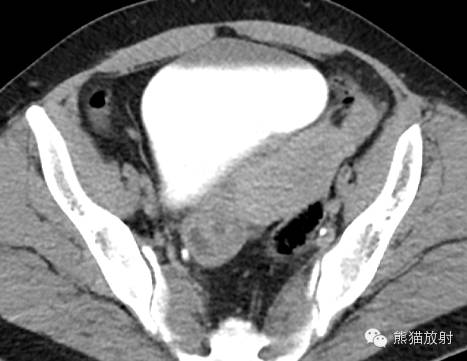

女,33岁,2年余前在月经期时,出现尿频、尿急,伴全程肉眼血尿,呈淡红色,无血块,有时可有尿痛;经期结束后,上述症状消失。

膀胱镜检查:膀胱三角区及各壁粘膜可见充血炎性改变,三角区后方可见一范围约1.5×2cm的粘膜隆起,局部可见紫蓝色的粘膜下瘀斑,于该处取病理2;

活检病理示:(膀胱)送检少许组织被覆尿路上皮,呈轻度慢性炎,间质中查见少数散在的腺体,结合临床和免疫表型,符合子宫内膜异位;免疫组化:ER 、PR 、CD10-、CK34βE12±、CK7±。

膀胱子宫内膜异位症

膀胱内异症 病理图(来自文献)

诸病灶分别如下图中圆圈所示: